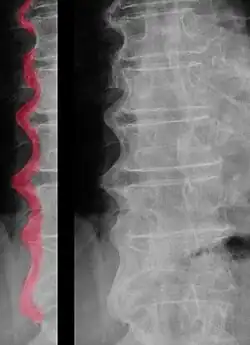

Die Diagnose einer DISH kann alleine auf Röntgennativaufnahmen gestellt werden. An den Wirbelkörpern sieht man im Röntgenbild einen meist rechtsseitigen zuckergussartigen Überzug von Knochenmaterial (Hyperostosen). Durch die Überbrückung der Bandscheibenräume ist die Beweglichkeit der Wirbelsäule in diesem Segment aufgehoben.